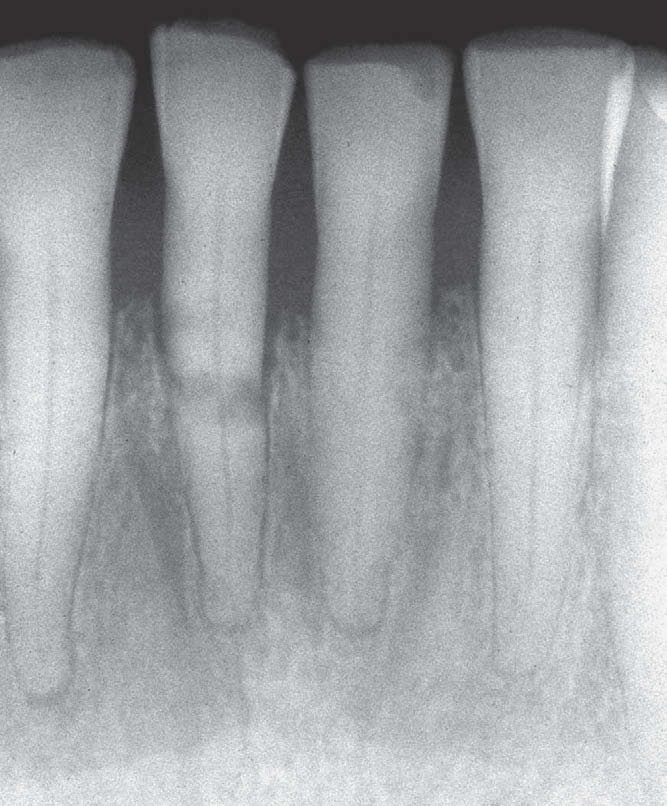

3. In the X ray bellow for which jaw periodontal bone loss is evident?

4. In the X ray bellow for which jaw periodontal bone loss is evident?